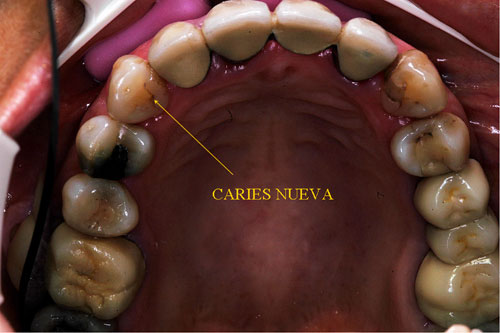

RESUMEN Mostración del Protocolo en R. O. y su desarrollo clínico. DESARROLLO Quienes realizamos Rehabilitación Bucal Integral desde muchos años atrás, siempre hemos buscado un protocolo coherente que nos permitiera ordenar el pensamiento cuando nos encontramos con aquellos caóticos casos donde marearse en la resolución es fácil y frecuente. PROTOCOLO DE ALONSO Sintéticamente consiste en otorgar al Sistema en primer término: Desoclusión en Lateralidades y Propulsiva de los sectores posteriores, mediante la construcción de la Guía Anterior tanto en los Provisorios como en los Definitivos, basados en el Encerado de Diagnóstico. PROTOCOLO PRÁCTICO (BASADO EN D.A.T.O.) Diagnóstico: clínico, radiográfico (donde no es necesario extenderse) y de laboratorio, donde mediante un encerado diagnóstico y otro de trabajo, conoceremos la fiel réplica de la boca del paciente antes de destruirse y los medios para reconstruirla basados en los procedimientos que podemos realizar en la cera. PRESENTACIÓN DEL CASO Se presenta la paciente derivada por un compañero a fin de consultar acerca de un primer molar superior izquierdo, a quien el Periodoncista aconsejaba realizar una radectomía debido a la pérdida ósea distal que dicha raíz presentaba. Dicha observación hace que decidamos tomar una actitud más conservadora, explicando al enfermo las razónes etiológicas de la pérdida ósea, y aconsejando quitar dicha funda para colocar una provisional morfológicamente correcta, y simultáneamente re-endodonciar y realizar la terapia básica periodontal. Visión Global del Caso Se observa a la inspección clínica y radiográfica, varios puentes fijos filtrados, como así también amalgamas de plata recidivadas. Inversión de la Curva de Wilson.(2º Elemento a nuestro alcance para obtener Desoclusión Se procede entonces luego de realizar los correspondientes modelos de yeso mediante impresiones precisas de alginato con cubetas Rim Lock, a tomar un registro cráneo maxilar mediante un arco facial estático (Artex) que nos permita montar el modelo superior respecto del Plano de Frankfurt con el punto Gnation de referencia. Luego, haciendo uso de las Laminillas de Long , (buscar referencias en el libro del Dr. Alonso o bien en múltiples publicaciones personales en Gaceta Dental o Maxillaris, como así también en mi propia web: en los artículos : RELACIÓN CÉNTRICA o AJUSTE OCLUSAL, BASES FILOSÓFICAS DE UNA OCLUSIÓN ORGÁNICA), (www.dracuna.com o www.oclusión.es,) . Procedemos a obtener el Registro Inter Maxilar de OCLUSIÓN EN RELACIÓN CÉNTRICA, mediante el cual, montamos el modelo inferior respecto del superior. Montamos así, en un Artex totalmente ajustable, pués no contábamos en ese momento con ningún semiajustable disponible,(ya que estaban todos ocupados), ajustando el Ángulo de Bennet y la Inclinación de la Trayectoria Condílea en gradaciones personalizadas mediante registros de Propulsión y Lateralidades). Procedemos entonces al estudio de los modelos. DIAGNÓSTICO GENERAL Disfunción oral generalizada, provocada por alteraciones en la Oclusión, en la Operatoria Dental, en la Endodoncia, en la Periodoncia y en la Prótesis realizada en esta boca a través de los años. Filtración generalizada de fundas. DIAGNÓSTICO PROTÉTICO OCLUSAL Carencia de guía canina. Carencia de alineación tridimensional en guía anterior. Carencia de curva de Wilson. TRATAMIENTO SUGERIDO 1-Encerado Progresivo de Diagnóstico y Trabajo de Peter K. Thomas. HEMOS OBTENIDO: D.AT.O Hasta aquí, hemos solo observado los elementos de diagnóstico clínicos, radiológicos y de laboratorio, como para comenzar a trabajar. AUTOR: Colaboración: CASO PRESENTADO EN LAS SESIONES CLÍNICAS DEL ILTRE. COLEGIO DE DENTISTAS DE MÁLAGA. Ratificación del Protocolo en Rehabilitación Bucal a pesar de las incidencias propias de cada caso clínico. A propósito de un caso.

Aconsejamos a la paciente realizar un estudio de toda la boca, ya que el molar en cuestión constituía apenas una muestra más de una odontología parcial, iatrogénica, y mal llevada, durante muchos años.

Realizamos fotografías de toda la boca y la correspondiente ortopantomografía apoyada por imágenes de laser visiografía seriada, estudio inicial mínimo necesario para diagnosticar el funcionamiento del SEG.